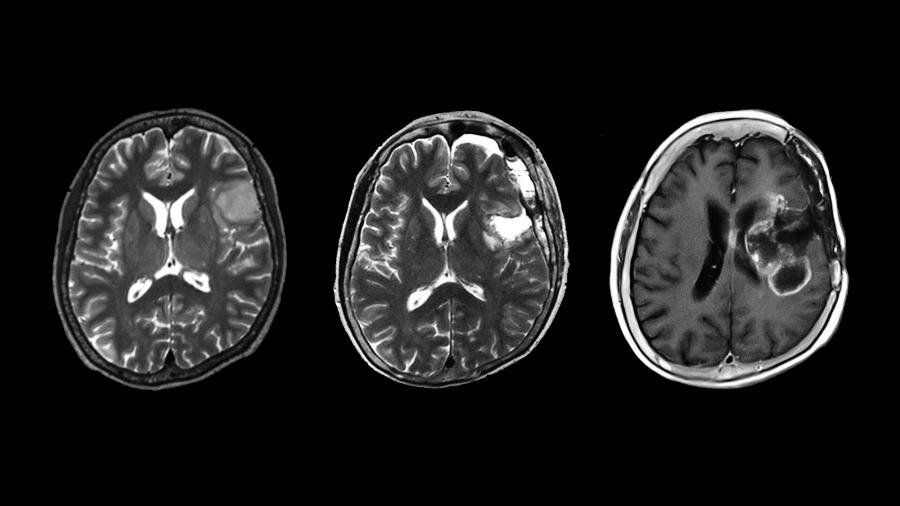

През 2016 г., за да се подобрят прогнозата и лечението на пациентите, класификацията на СЗО на туморите на централната нервна система включва нова класификация на дифузните глиоми въз основа на наличието или липсата на специфични мутации. Два редки вида дифузни астроцитоми са инфилтративните и локализираните дифузни астроцитоми с див тип изоцитрат дехидрогеназа (IDHwt). Тъй като те са толкова редки, липсва информация дали инфилтративните или локализираните характеристики влияят на прогнозата им и какво означава това за пациента.

Изследователският екип от Университета в Нагоя, ръководен от Юджи Кибе и Казуя Мотомура от Катедрата по неврохирургия, анализира локализираните IDHwt астроцитоми и установява, че всички те водят до злокачествени рецидиви и лоша клинична прогноза, подобна на тази при глиобластомите. Глиобластомите са сред най-злокачествените тумори, като средната им преживяемост е осем месеца, а по-малко от 7% от пациентите преживяват пет години.

Мотомура смята, че откритията на екипа са важни за лекарите и пациентите. "Всички тумори, които изследвахме, имаха мрачна прогноза въпреки мултидисциплинарното лечение", казва той. "За пациентите с глиоми резултатите от нашите изследвания трябва да доведат до поставяне на правилна клинична диагноза и лечение. За лекарите IDHwt астроцитомите трябва да се проследяват с голямо внимание дори след пълното им отстраняване. Трябва да се обмисли силна следоперативна терапия. Тъй като почти всички пациенти с дифузни астроцитоми се представят с рентгенографски образни находки, предполагащи локализирана туморна маса, лекарите могат да поставят погрешна диагноза на пациента с нискостепенен тумор вместо със злокачествен тумор; следователно нашите резултати предполагат, че лекарите трябва да обмислят възможността за такива тумори."